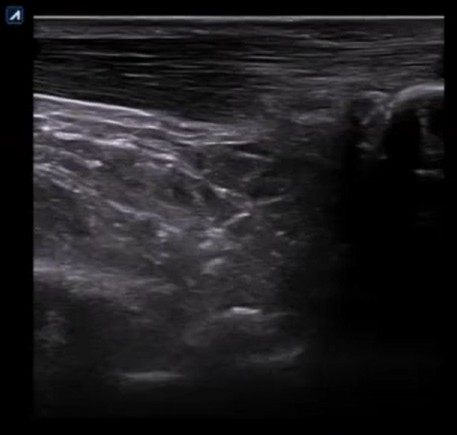

Rotura parcial del tendón de Aquiles: interfase profunda

En esta imagen se puede ver una zona anecoica en la interfase profunda del tendón. Se puede observar una pérdida de continuidad del patrón fibrilar de las fibras tendinosas.

Por la localización de la zona anecoica, podría confundirse con una bursitis. No obstante, en una bursitis las fibras tendinosas posteriores mantendrían su continuidad (a diferencia de la imagen anterior).